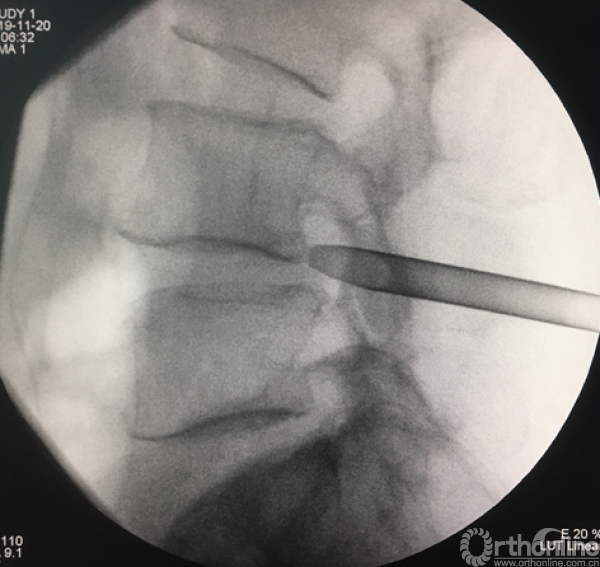

放入工作套管

正侧位透视确定责任节段

植入试模判断融合器大小